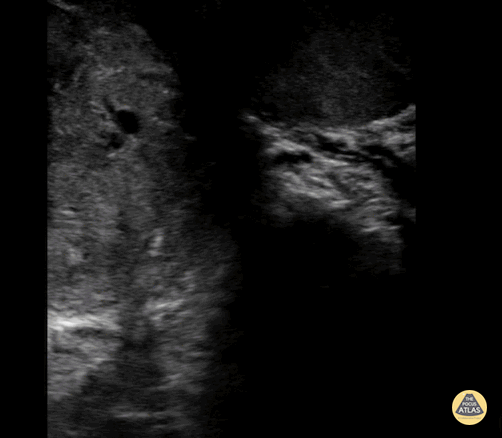

16 year old male with right testicular pain and swelling presented to the emergency department, a POCUS was done showing increased flow in the left testicle along with surrounding edema. This ultrasound clip demonstrates the enlarged testicle with surrounding edema. Diagnosis of orchitis was made and confirmed with radiology performed ultrasound. Contributor: Zach Boivin, MD, @ZachBoivinMD